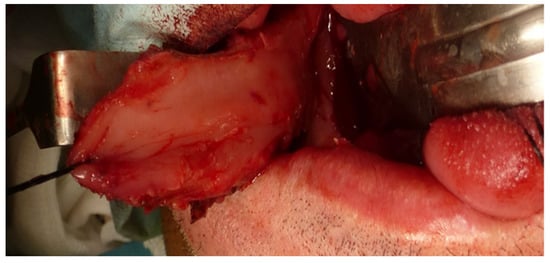

A homolateral selective cervical dissection with resection of the tumor of the tongue and floor of the mouth with free margins was performed. The defect to be reconstructed was 5.7 × 3.6 cm and a FAMM flap was designed for reconstruction (Figure 2).

Figure 3. Right FAMM flap inferiorly pedicled with an anterograde flow on the facial artery.

Jcm 10 03625 g003

Figure 4. Immediate reconstruction of tongue and floor of the mouth defect.

Jcm 10 03625 g004